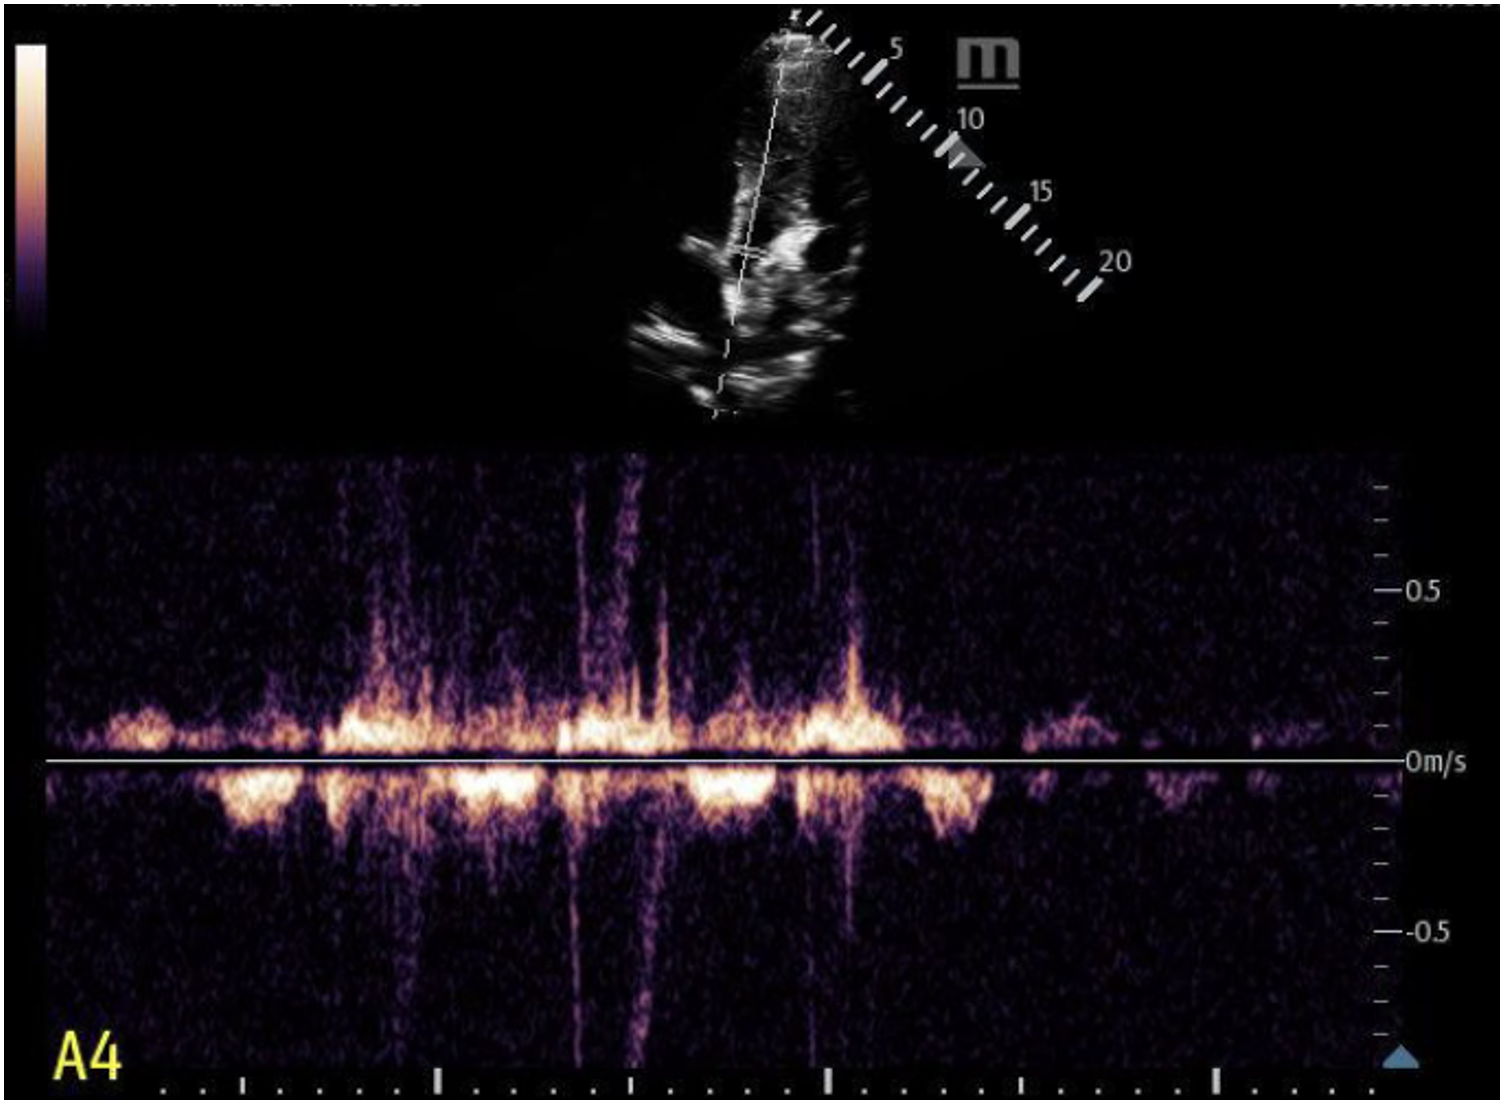

Finding #4: Left Ventricular Outflow Tract Obstruction (LVOTO)

• View: A5 View with Continuous Wave Doppler

• Doppler will show “dagger-like/shark fin” waveform (produced by a late systolic peak)

• Measure peak velocity to obtain a gradient

• Gradient > 30 mmHg indicates obstruction

• ⅓ of HCM patient will have a high gradient at rest

• ⅓ of HCM patients will have a high gradient with provocation (Valsalva, exercise, medication)

• ⅓ of HCM patients will have no obstruction

This is where you would place your Continuous Wave Doppler axis.

We used M Mode on the mitral valve and did not see SAM.

We used continuous wave doppler in a limited A5 view. We did not see any obvious “dagger-like” or “shark fin” waveforms.